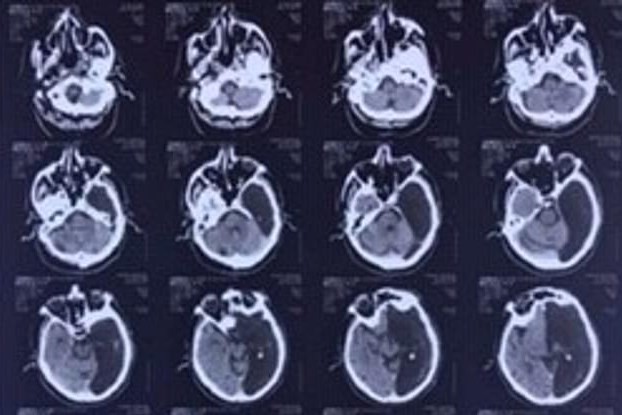

Según informa el Daily Mail, los médicos le realizaron una tomografía computarizada, dándose cuenta que tenía un "agujero negro" al interior de su cráneo.

Un hombre de 60 años sufrió un mini accidente cerebrovascular, por lo cual terminó en un hospital de su natal Rusia. Lo curioso es que los médicos rápidamente se olvidaron de su problema, ya que lo que hallaron fue impactante: le faltaba la mitad del cerebro.

Al respecto, indicaron que el hemisferio derecho del paciente funcionó correctamente y cumplió con todas sus labores que le correspondían a ella y al de la zona izquierda, sin presentar el individuo ningún problema en toda su vida que tenga como origen lo que le faltaba de cerebro.